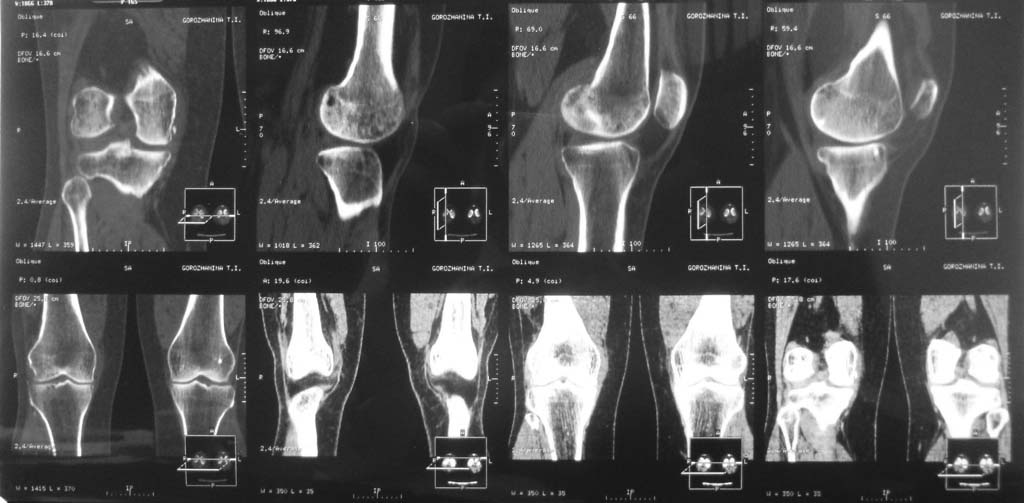

Пациентка Г. 50 лет

жалобы на боль в коленном суставе в течении 1 года. консультирована краевым ортопедом

выставлен DS: Синдром медиопателярной связки коленного сустава. Тактика дальнейшего

ведения.